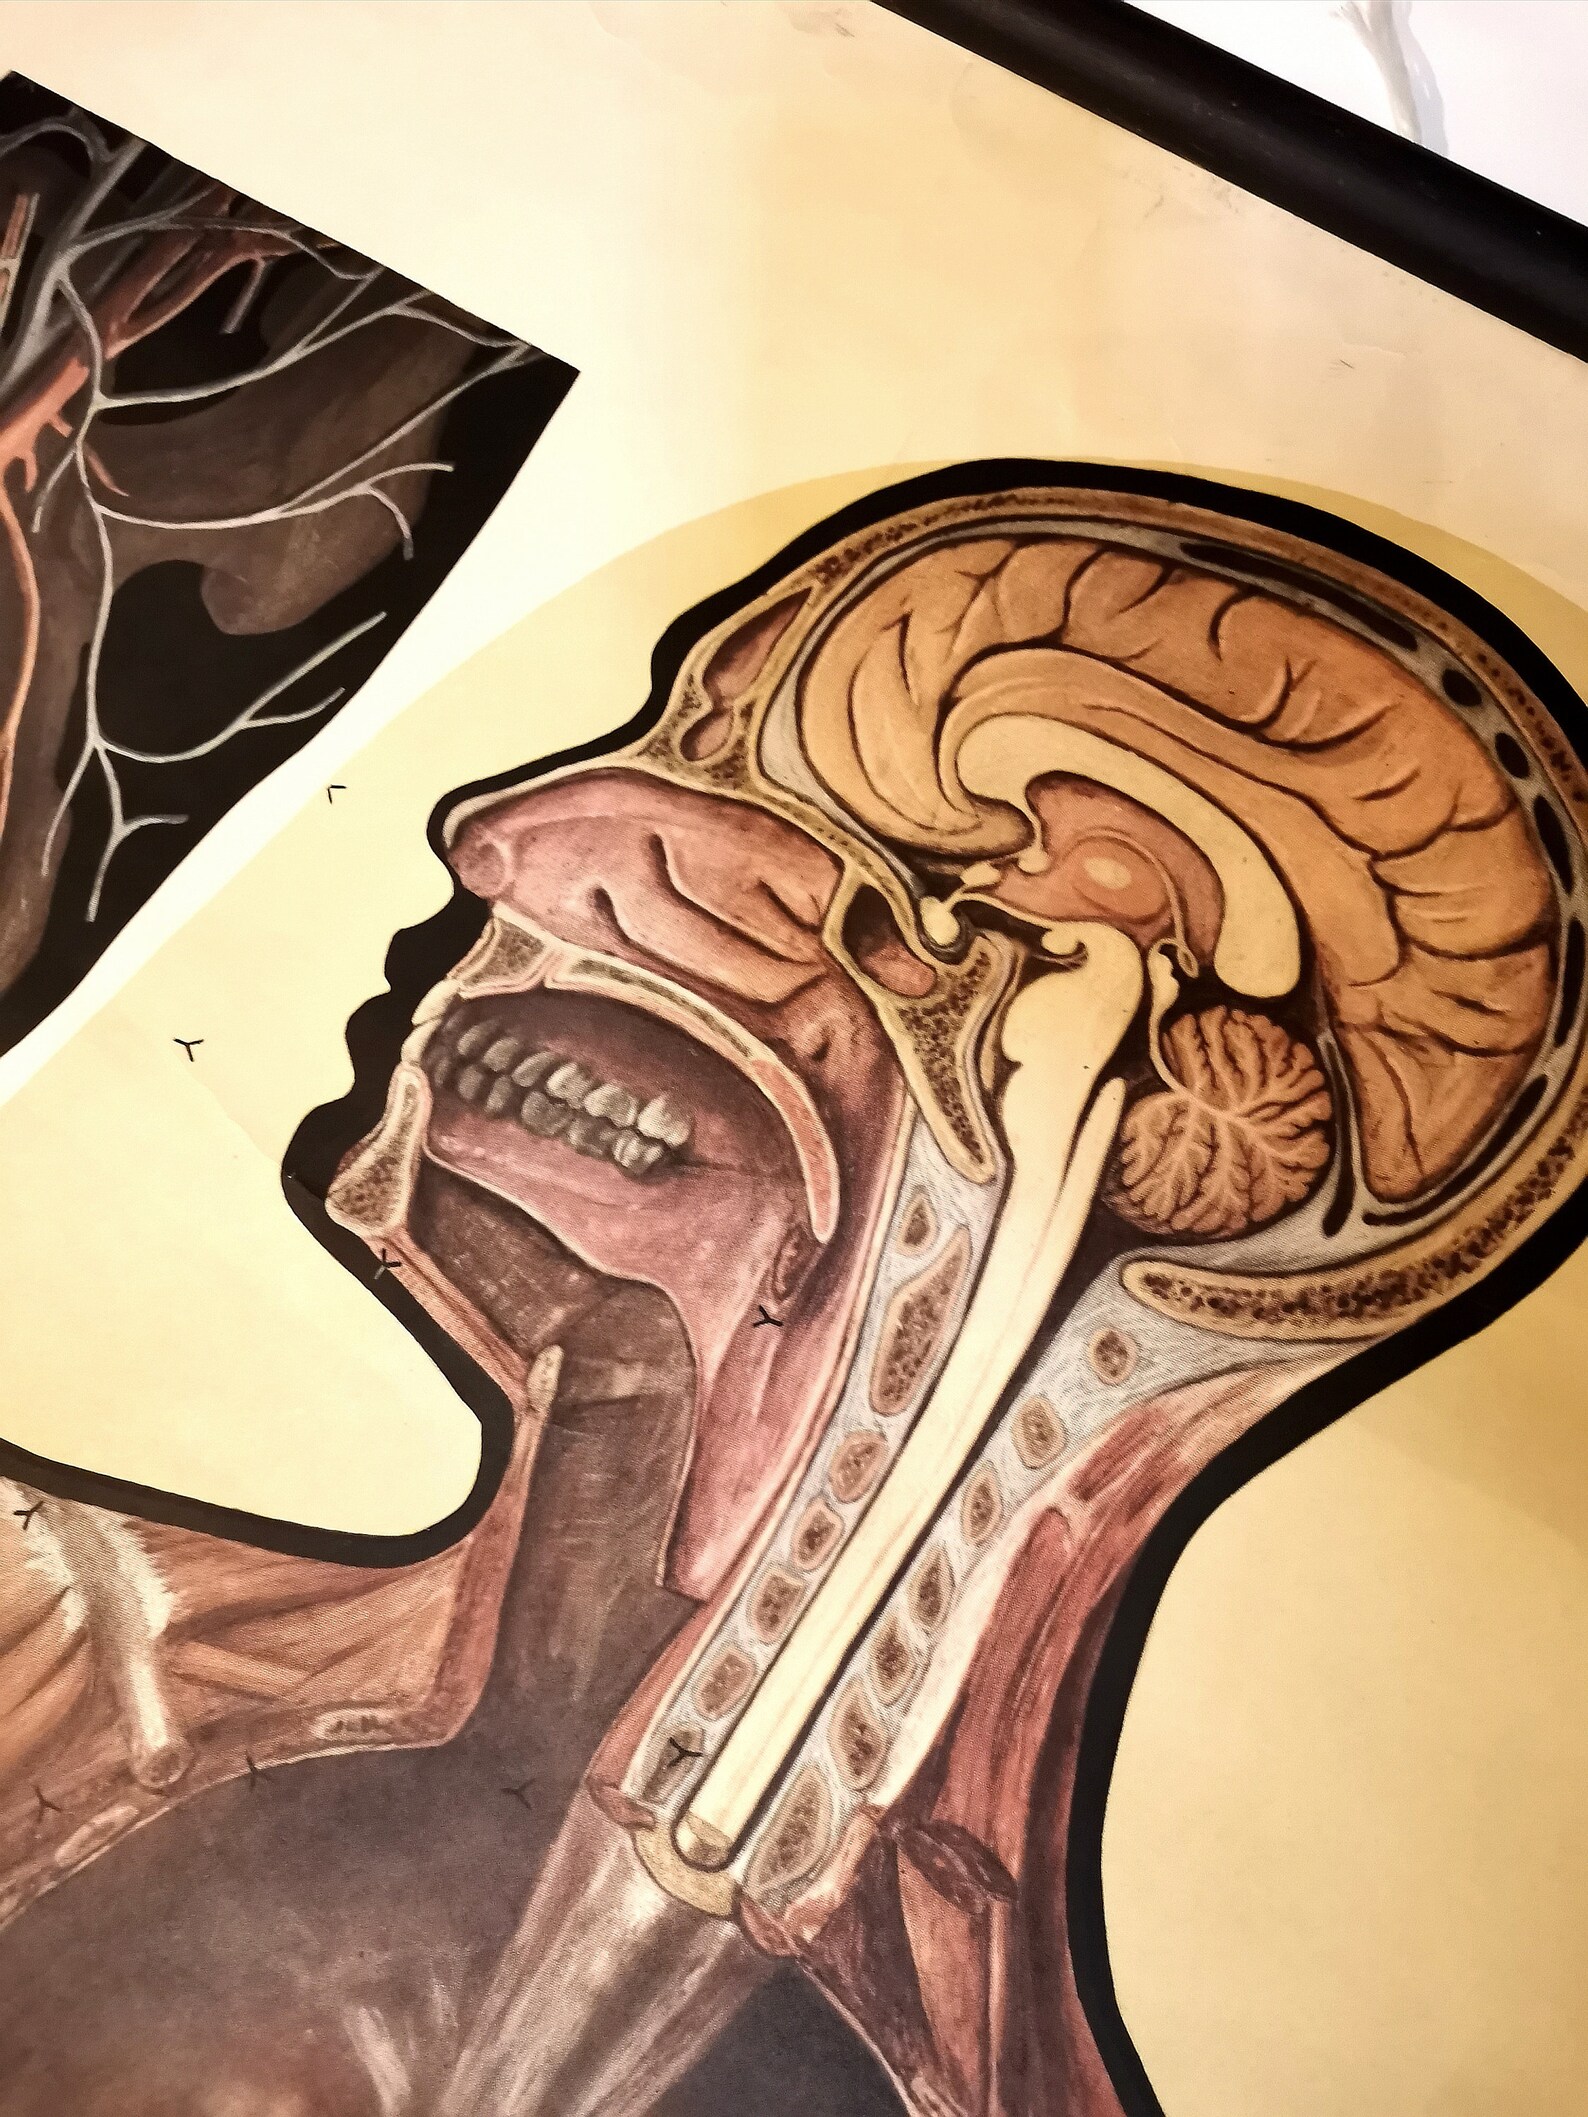

www.etsy.comAuthentic Vintage Anatomy Human Body School Educational Poster - Etsy

www.etsy.comAuthentic Vintage Anatomy Human Body School Educational Poster - Etsy

www.etsy.comauthentic

www.etsy.comauthentic

www.redbubble.comAuthentic Vintage Anatomy Human Body School Educational Poster - Etsy

www.redbubble.comAuthentic Vintage Anatomy Human Body School Educational Poster - Etsy